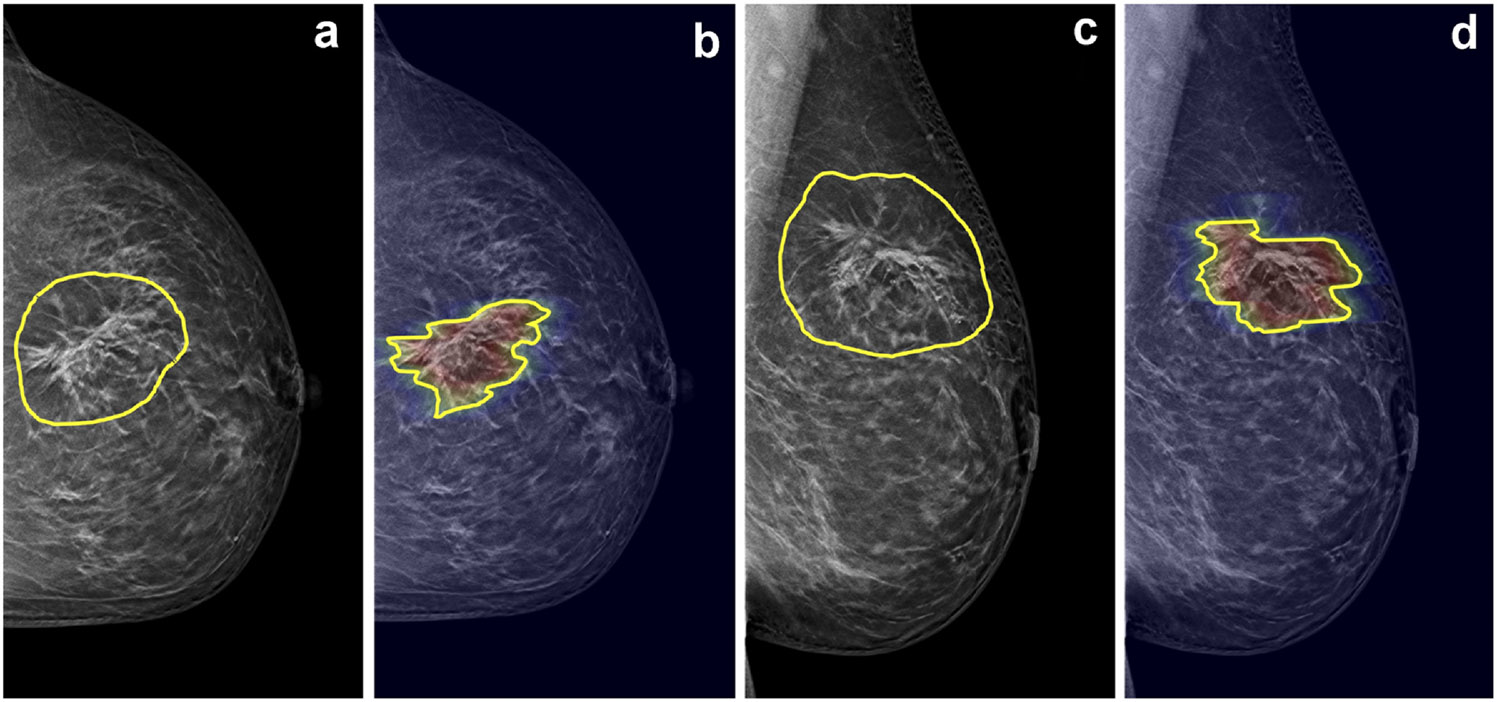

Figure 4.

A malignant case of pure architectural distortion from a 47-year-old patient confirmed with invasive ductal cancer. The DBT BI-RADS score is 4B. The radiomics score from manual ROI is 0.47, false negative. The radiomics score from DL-generated ROI is 0.64, true positive. (a) CC view DBT image with manual ROI, (b) CC view DBT image overlaid with heat map from Grad-CAM and the DL-generated ROI, (c) MLO view DBT image with manual ROI, (d) MLO view DBT image overlaid with heat map from Grad-CAM and the DL-generated ROI.